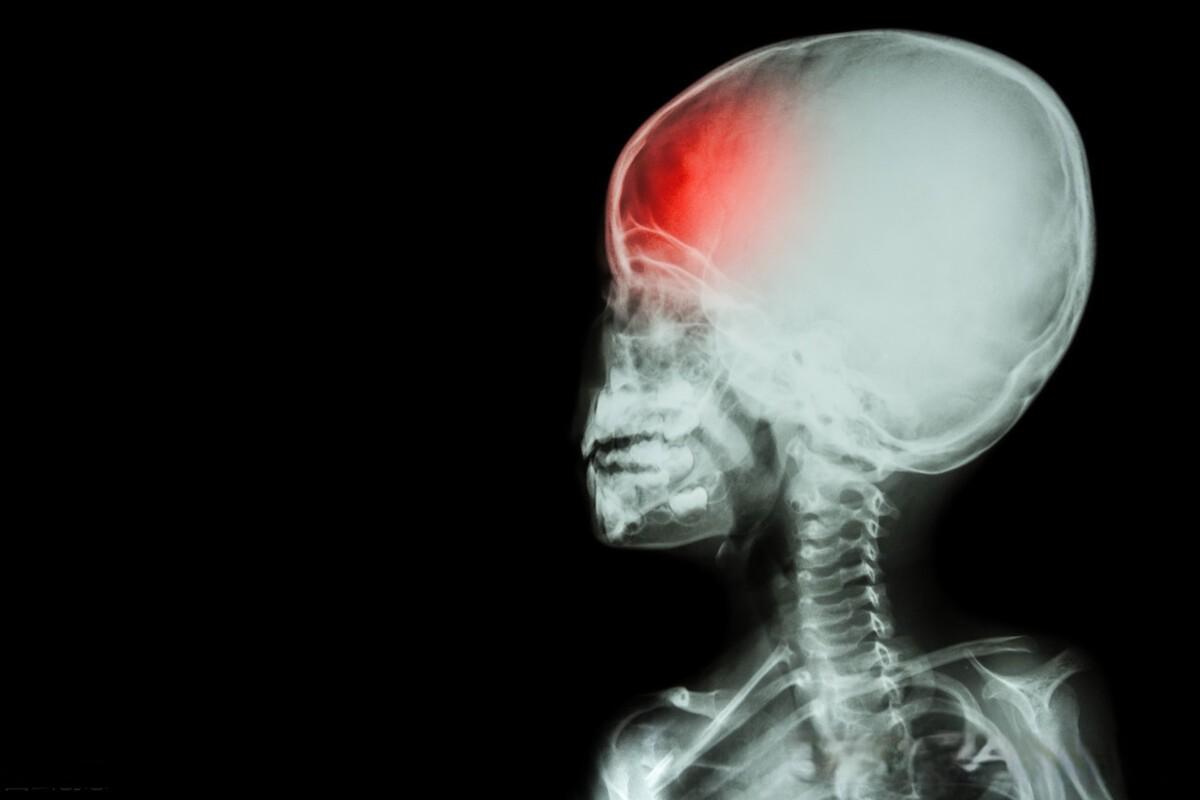

治疗中风的方子:中风后遗症,半身不遂就用补阳还五汤

在中医理论中,中风后遗症多由气虚血瘀所致。正如《医林改错》所言:“此方治半身不遂,口眼歪斜,语言謇涩,口角流涎,下肢痿废,小便频数,遗尿不禁。”补阳还五汤通过重用黄芪以补元气,配以当归尾、赤芍等活血化瘀之品,达到气旺血行、瘀去络通的效果。这种“补阳还五”的理念,体现了中医“因虚致瘀”的病理认识。